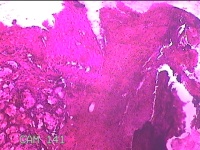

左侧鼻腔新生物

性别

女

年龄

43岁

临床诊断

1.慢性鼻窦炎 2.鼻息肉 3.鼻中隔偏曲 4.鼻腔粘连 5.变应性鼻炎

一般病史

鼻塞、脓涕3月余。’

标本名称

大体所见

灰白暗红色不规则肿物1.3x0.3x0.2cm一个,表面糜烂,内有少许骨质。

图3